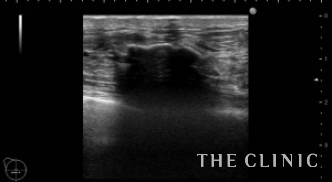

10年前に脂肪注入をされた方です。エコーでみると、右胸の下方に25㎜大のしこりがあり石灰化しています。中身はオイルと古い脂肪です。左胸上方には13㎜大のしこりがあり、中身はオイルです。右の石灰化しているしこりは、被膜が薄いためベイザーで崩していきます。左のしこりは穿刺処置となりました。

右)石灰化しているしこりにベイザーを突き刺します。 左)ベイザーで崩して吸引したあとですが、石灰化しているためカプセルが残存しています。